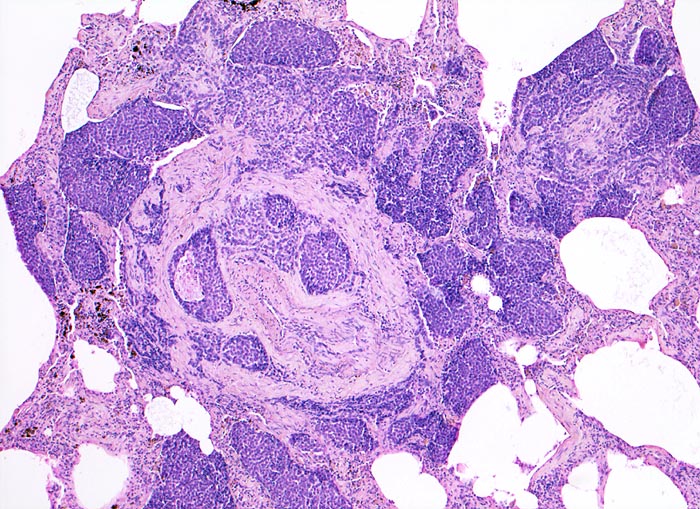

• Das Karzinom ist aufgebaut aus tubulären und kribriformen Drüsen.

• In den sternförmigen Ausläufern finden sich erweiterte Endothelausgekleidete Lymphgefässe in der Nachbarschaft von Blutgefässen.

• Die erweiterten Lymphgefässe enthalten solide Tumorzellaggregate.